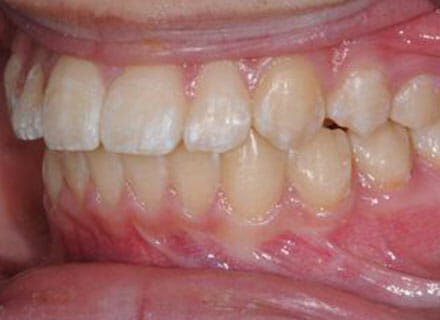

Fixing protruding teeth upper and lower and crowding – no extractions

this patient didn’t like the teeth because they pushed forwards and were sticking out and pushing out her lips. She thought that she looked like she had too many teeth and not enough space. In 12 months we pulled all the teeth back, pulled them together, and lined them all up. No teeth were extracted because we made room by expanding the jaws.